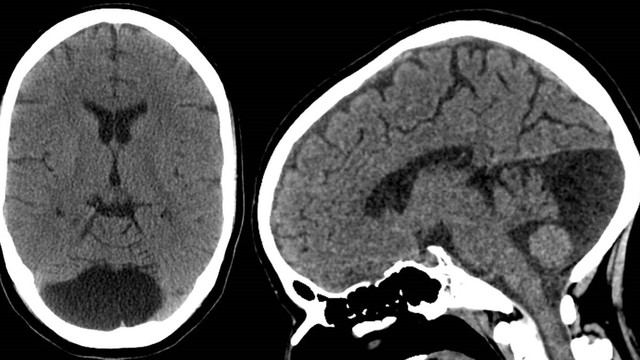

U nang màng nhện là một túi chứa chất lỏng phát triển trên não hoặc tủy sống. Chúng không phải là khối u và không phải là ung thư. Trong một số trường hợp hiếm, nếu chúng phát triển quá lớn đè lên các cấu trúc khác, có thể gây tổn thương não hoặc các vấn đề về vận động. Bài viết hôm nay sẽ giúp mọi người hiểu rõ hơn về bệnh lý u nang màng nhện.